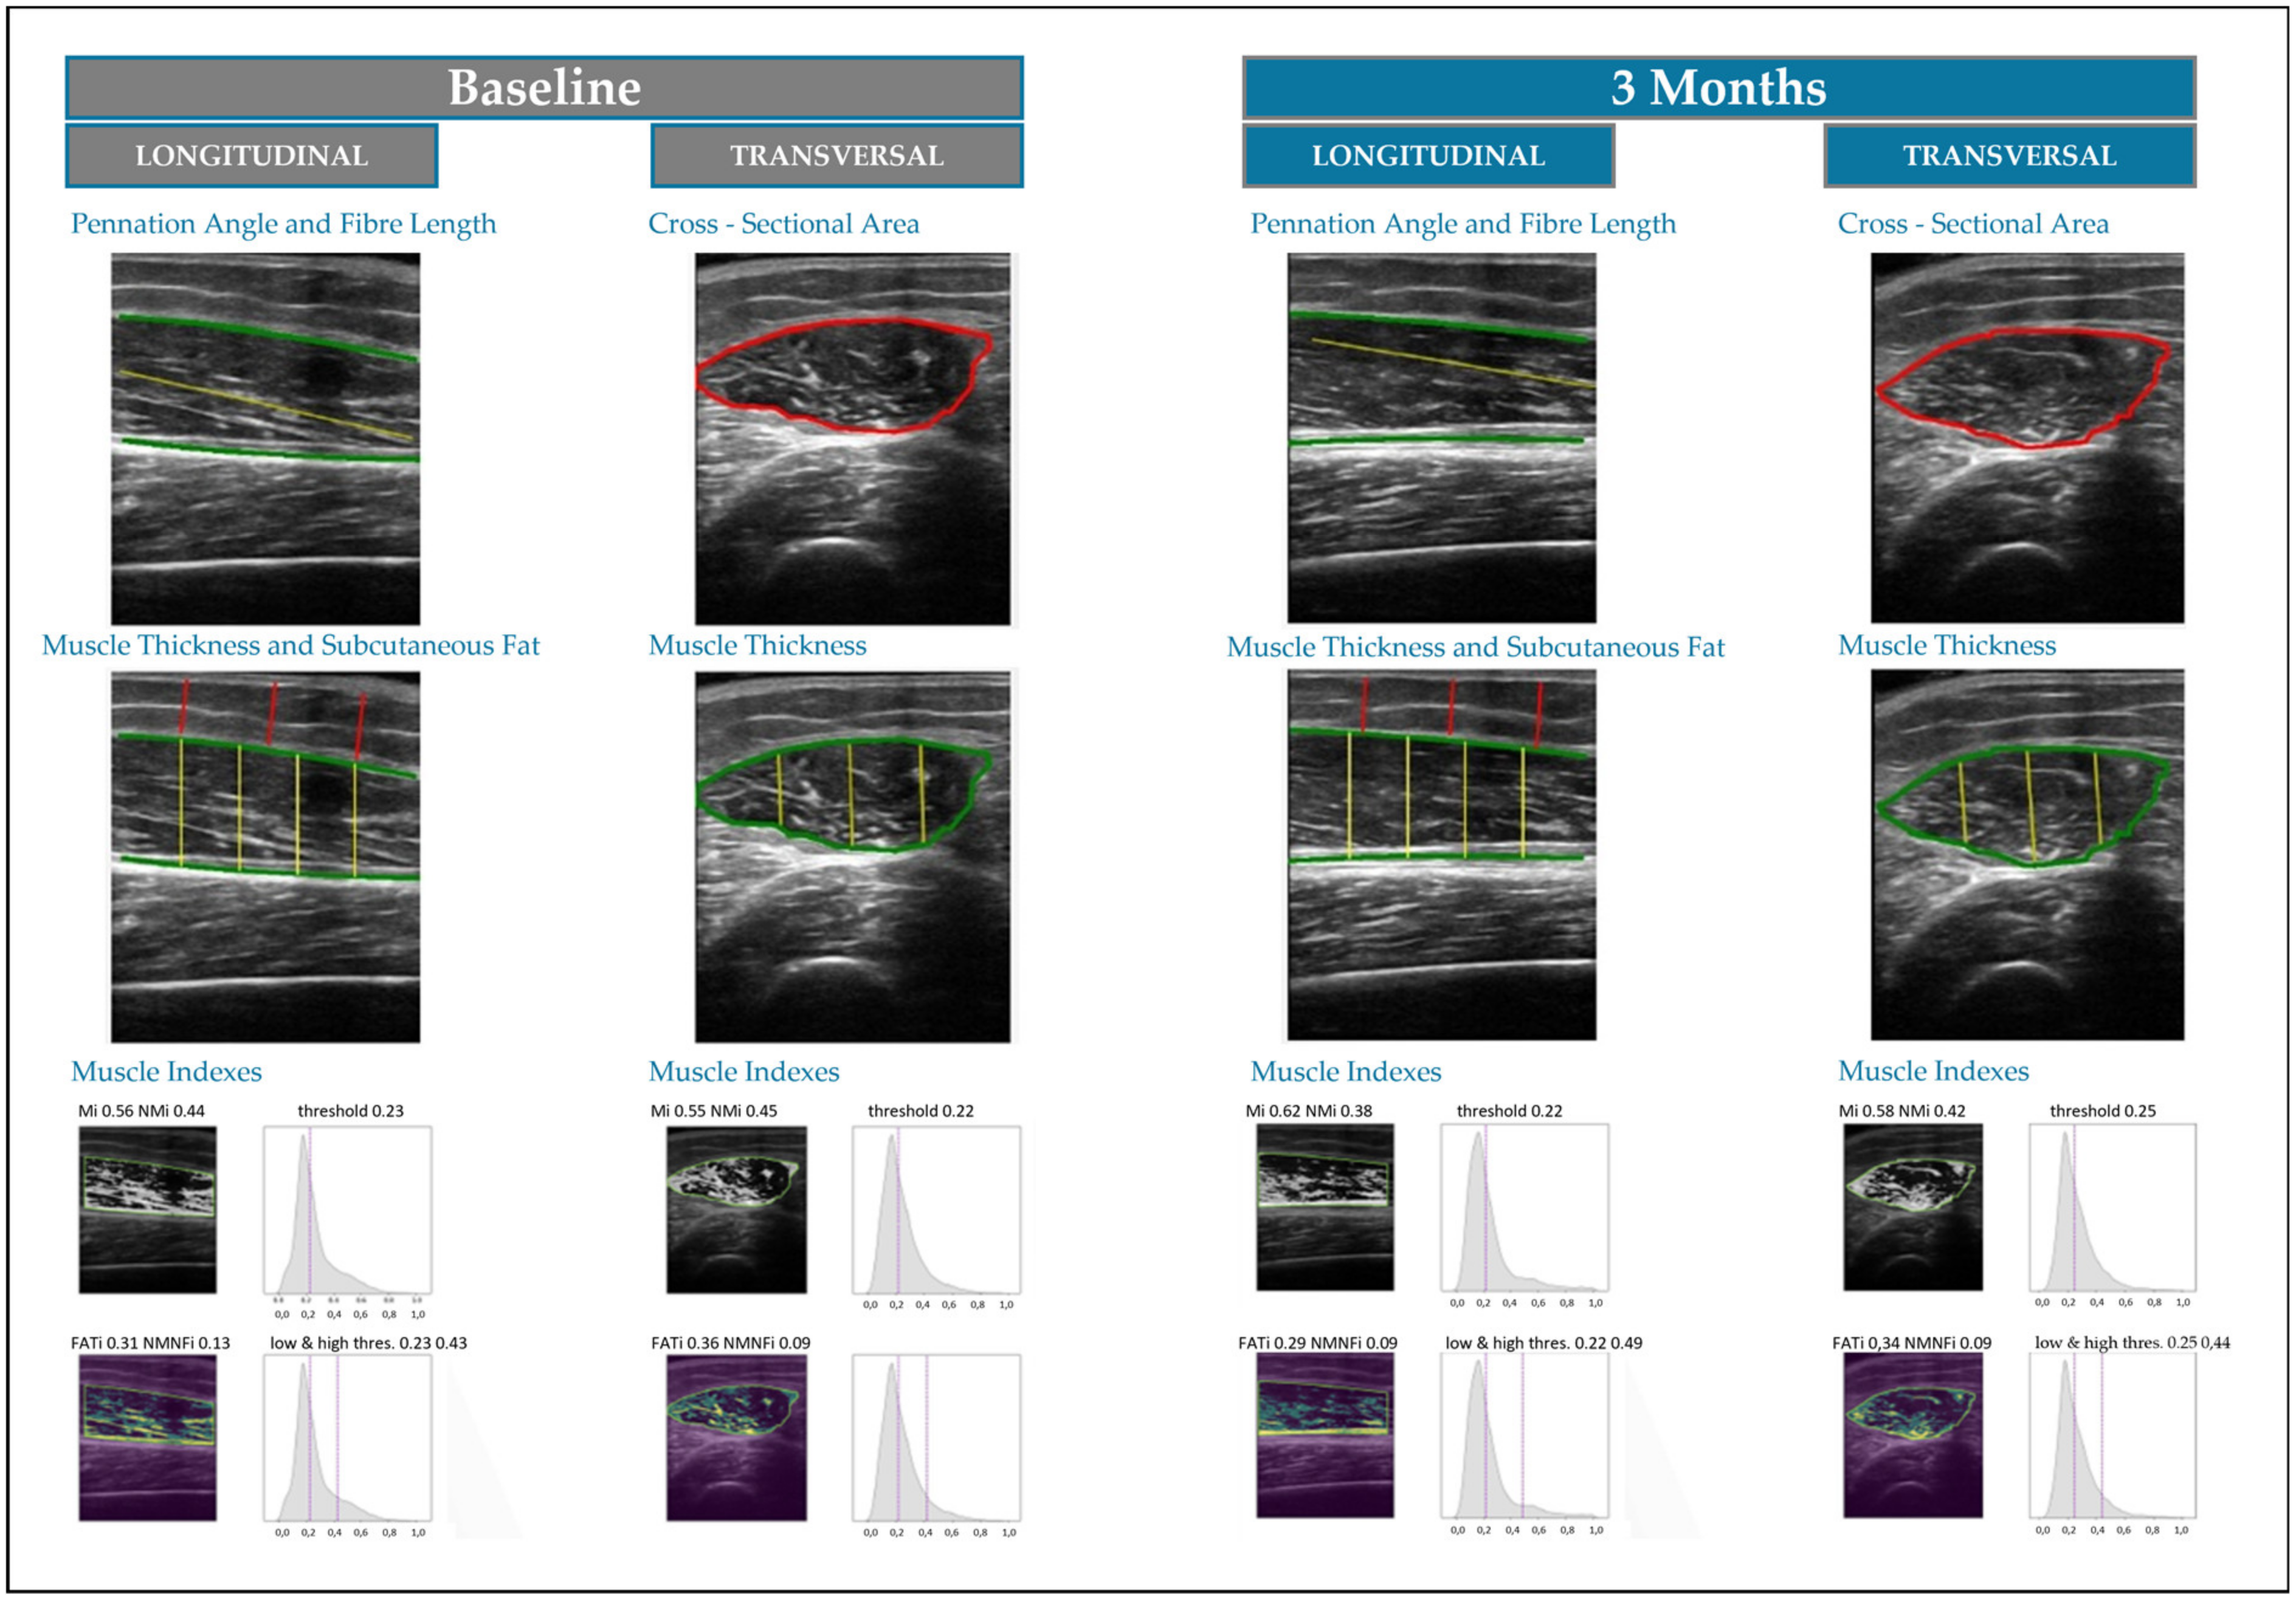

- García-Herreros, S.; López Gómez, J.J.; Cebria, A.; Izaola, O.; Salvador Coloma, P.; Nozal, S.; Cano, J.; Primo, D.; Godoy, E.J.; de Luis, D. Validation of an Artificial Intelligence-Based Ultrasound Imaging System for Quantifying Muscle Architecture Parameters of the Rectus Femoris in Disease-Related Malnutrition (DRM). Nutrients 2024, 16, 1806. [Google Scholar] [CrossRef]